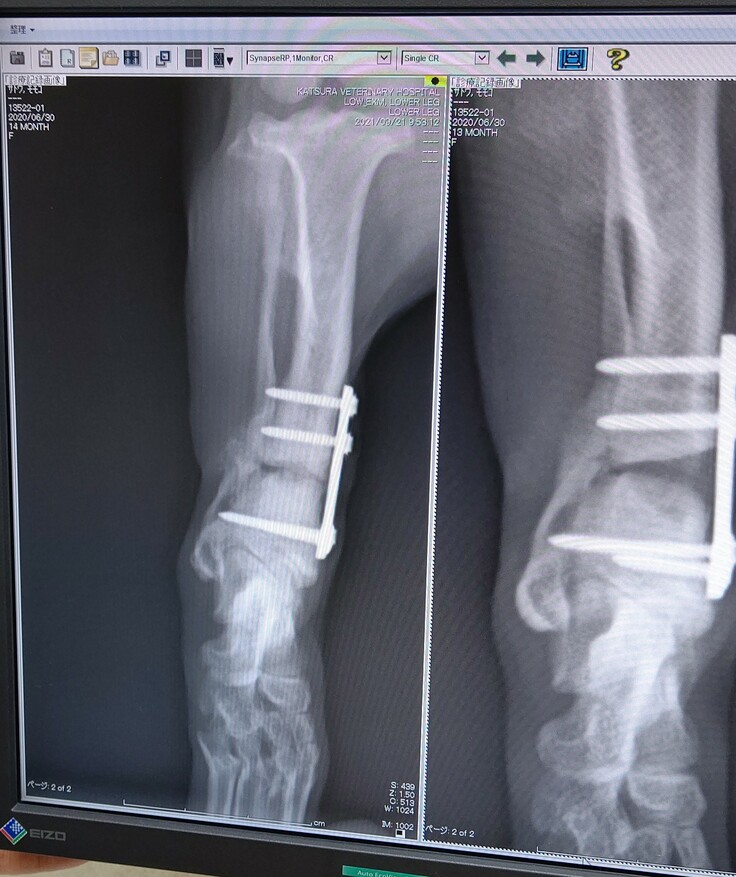

9/21今日のももちゃん

本日検診でした。

経過は良好!順調です。

隙間が見えますが

骨はほぼ埋まっているということです

それにしても

こんなプレートが両足に埋まっているなんて

ももちゃんはサイボーグです。